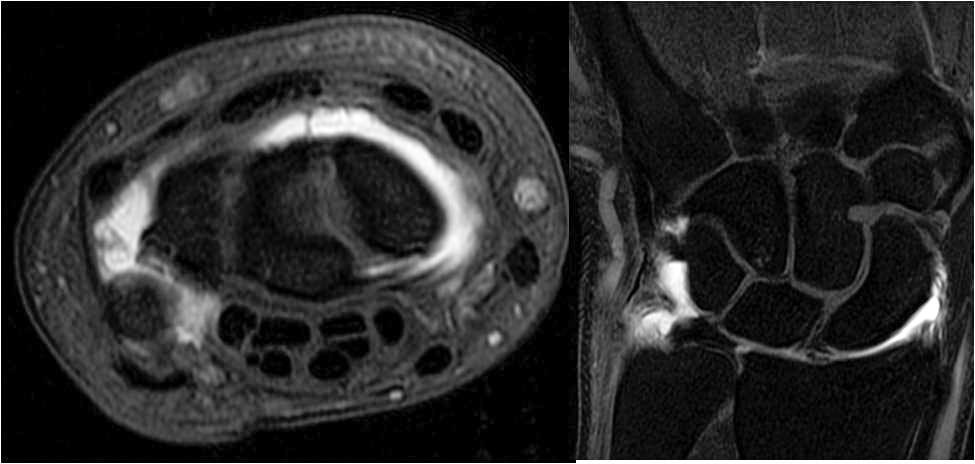

• To train fellows to become efficient, practical, and skilled in the multi-modality imaging of rheumatologic disease and sports related injuries including conventional radiography, CT, arthography, ultrasound and MRI.

• To train fellows to become proficient in orthopedic oncologic imaging including conventional radiography, ultrasound, CT, and MRI.

A wide range of diagnostic services including radiography, US, CT, MRI, and arthrography are complemented by an active MSK interventional service providing diagnostic arthrography, joint injections, and bone and soft tissue biopsies.

The fellows responsibilities include assisting the attending staff in resident education and training. The fellowship focuses on achieving a comprehensive understanding of the basic principles of MSK imaging including MRI and CT imaging protocol optimization for sports medicine, bone and soft tissue neoplasms, rheumatologic disease and arthrography.